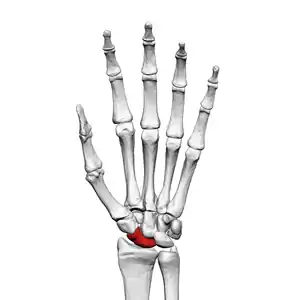

The scaphoid bone is one of the carpal bones of the wrist. It is situated between the hand and forearm on the thumb side of the wrist (also called the lateral or radial side). It forms the radial border of the carpal tunnel. The scaphoid bone is the largest bone of the proximal row of wrist bones, its long axis being from above downward, lateralward, and forward. It is approximately the size and shape of a medium cashew nut.

The scaphoid is situated between the proximal and distal rows of carpal bones. It is located on the radial side of the wrist,[1]: 176 adjacent to the styloid process of the radius.[2] It articulates with the radius, lunate, trapezoid, trapezium, and capitate.[1]: 176 Over 80% of the bone is covered in articular cartilage.[3]